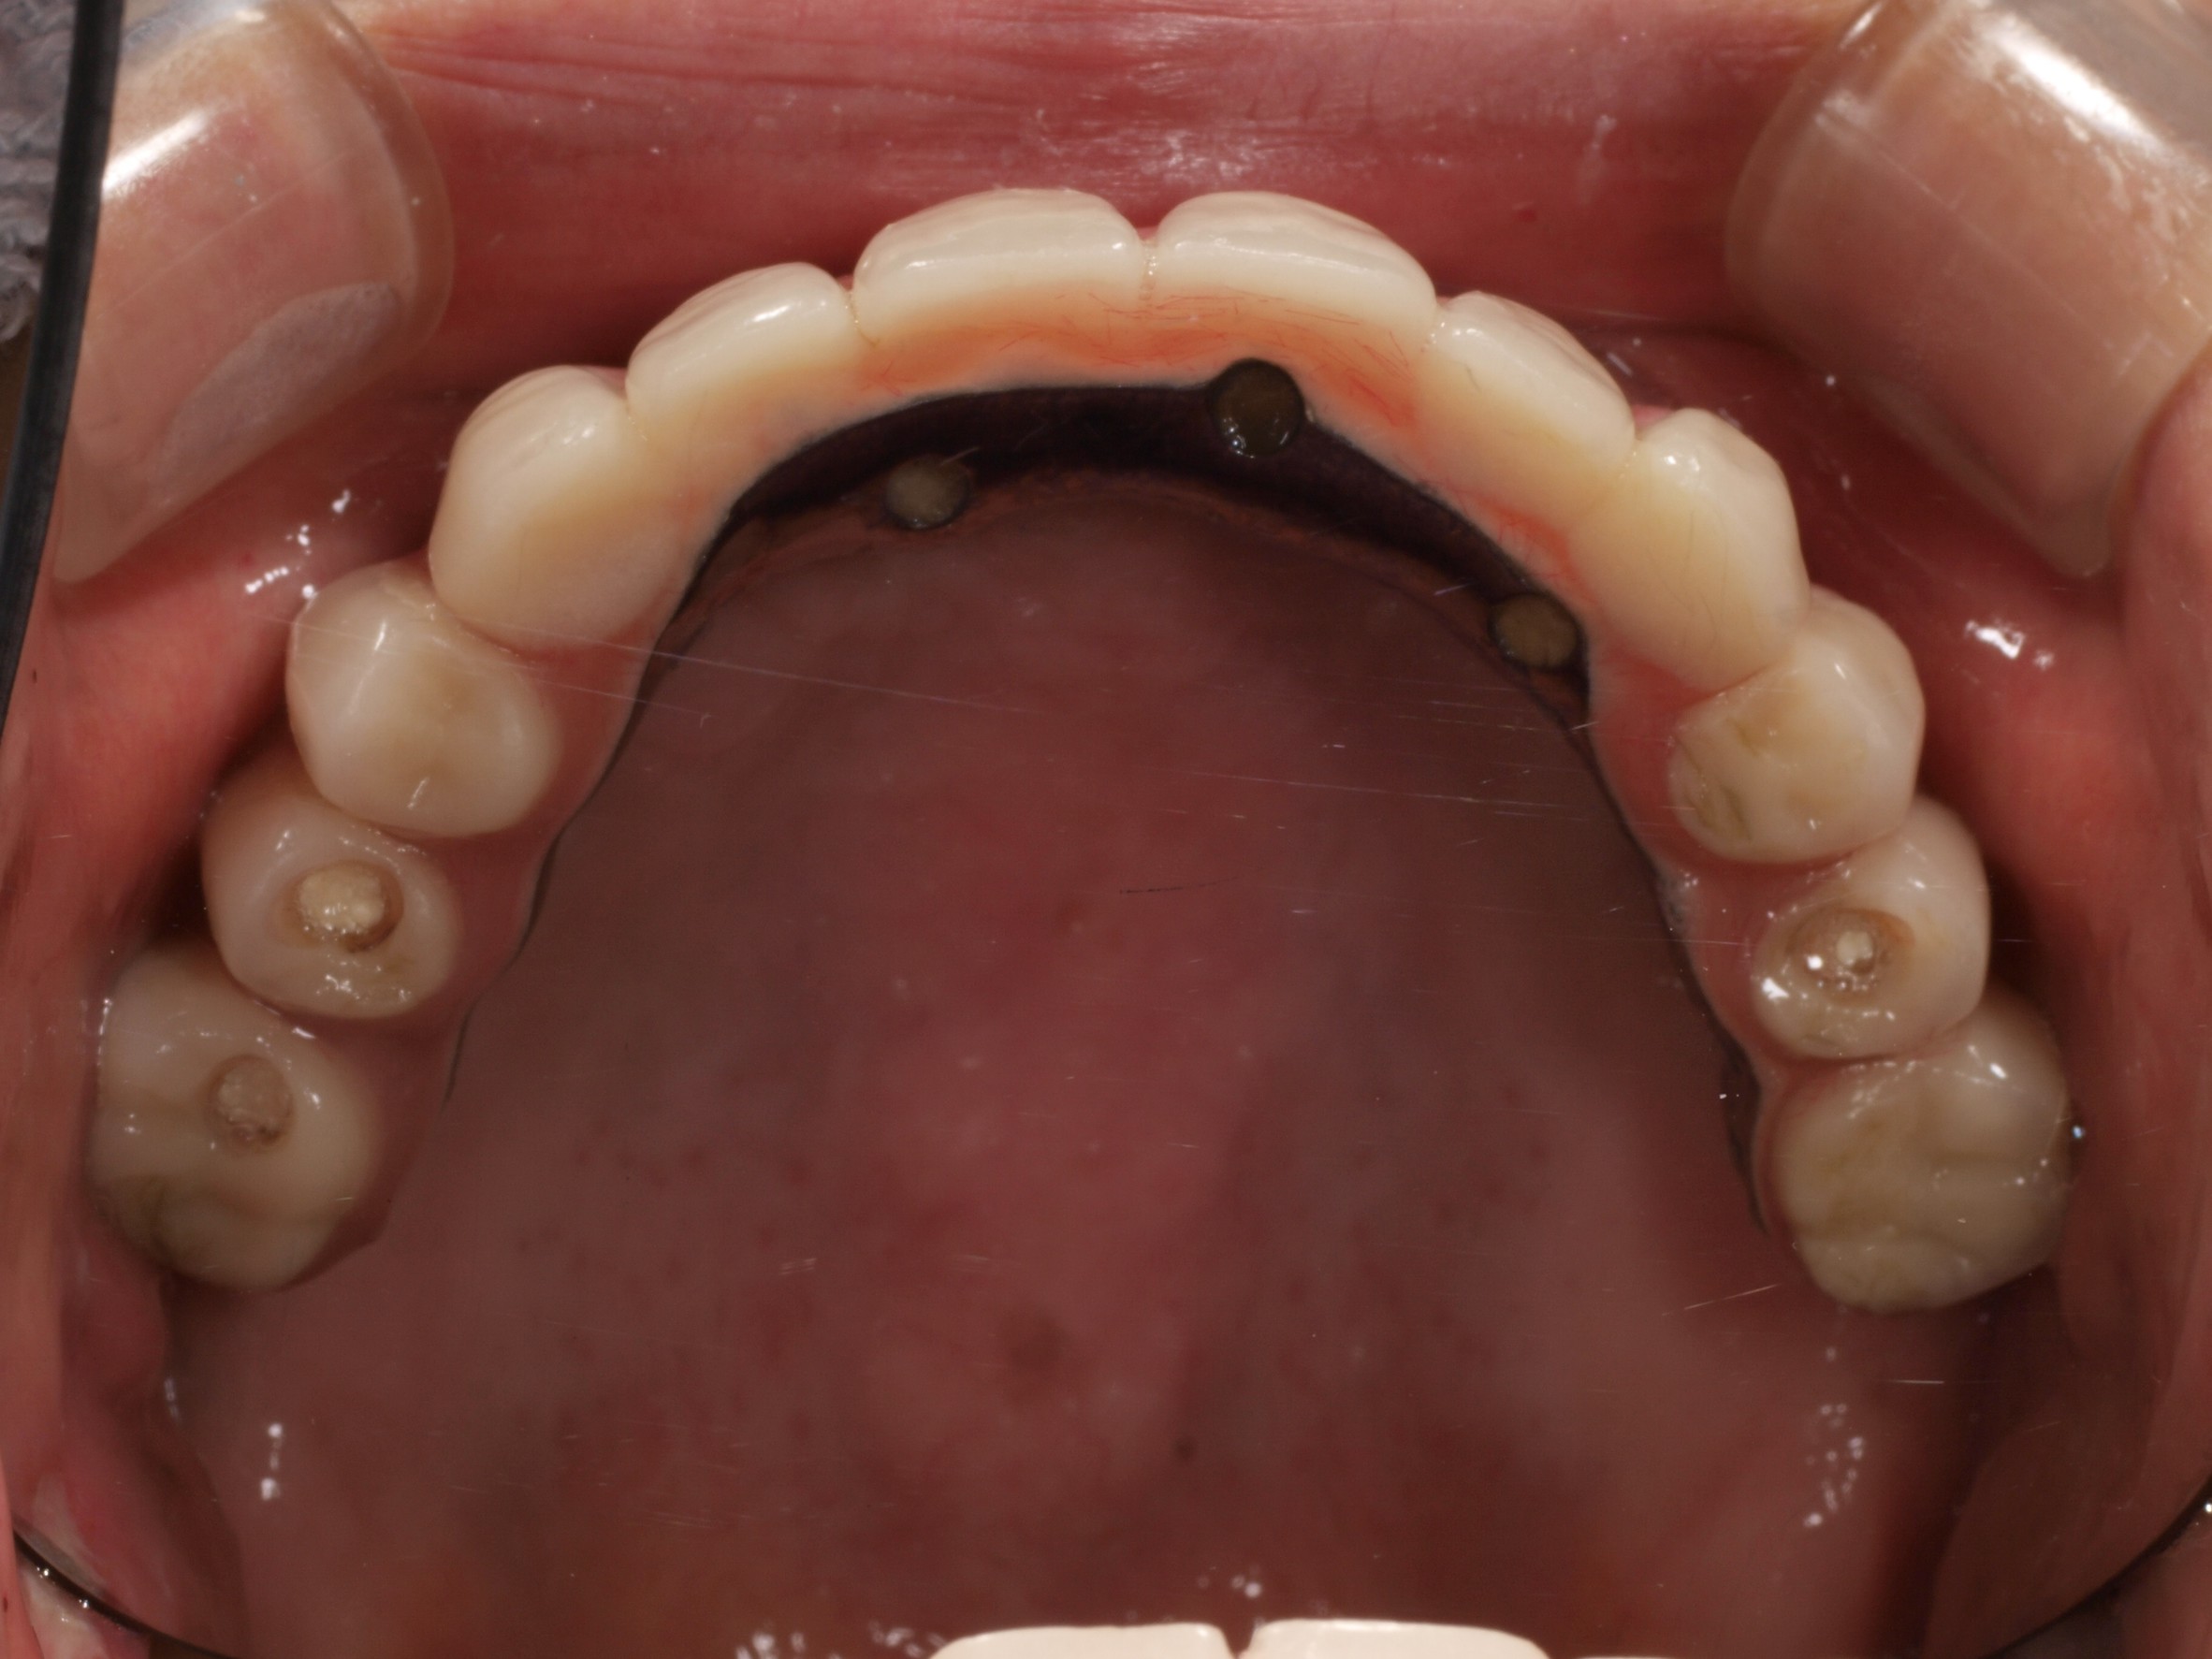

- 主訴

- 上顎入れ歯が辛い、下顎左右の歯が痛い、揺れる

- 処置内容

- 上顎6本(オールオン6) 下顎3本

- 治療費用

- 上顎:約350万円(税込)、下顎:約310万円(税込)仮歯まで5か月)

- 治療期間

- 上顎:1年(仮歯まで8か月)/約10回

下顎:8か月(仮歯まで5か月)/約7回

- リスク

- 上部構造物、仮歯の破折、術後の腫れ(3日)、人工歯根脱落リスクがあります